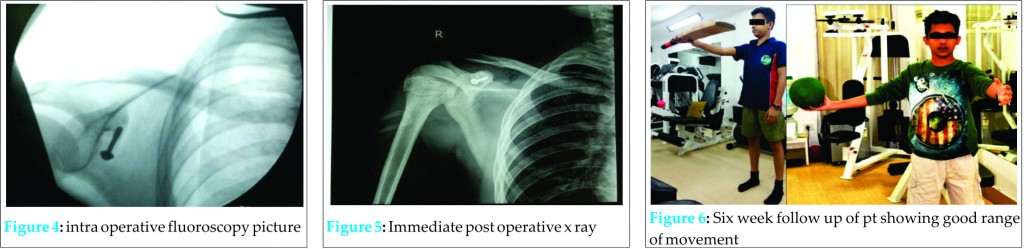

Coracoid fracture was an isolated fracture with no other associated fracture clinically or radiologically. The patient was admitted for surgery taking consideration of the age and profession of the patient. After making the incision along the Langer’s line on the coracoid process, the fracture line was reached. After open reduction, fixation was made with a 3.5mm cannulated screw with a washer (Fig. 4). Intra operatively the fragment was assessed to be reduced well.

In immediate post operative X-ray, both screw & the fragment were found to be in proper position (Fig. 5).

Postoperatively, the patient was followed up for 2 weeks with the application of a simple shoulder sling. Passive joint exercises were allowed in the first 2 weeks; from the 3rd postoperative week, active joint movement exercises were started and 5th week onwards shoulder strengthening exercises were commenced. The bone was united and fracture had healed as there was no pain at the fracture site and also muscle strength was adequate at the end of 6th post operative week. The patient returned to his previous occupation pain free and with a full range of joint movement (Fig. 6). The patient was followed up for next 6 months and there was no complaint of pain and difficulties in bowling.